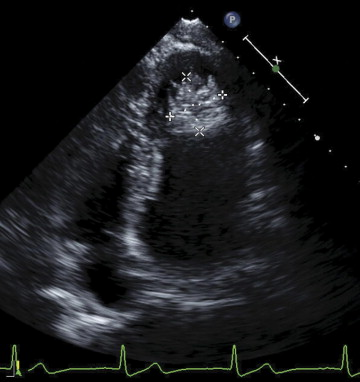

LV Thrombus

Features:

• regional wall motion abnormality

• apical location

• distinct margin with jagged edges

• movement separate from the underlying endocardium

• higher echo density as compared with the myocardium

Back to the Case

LV Thrombus post Anterior MI